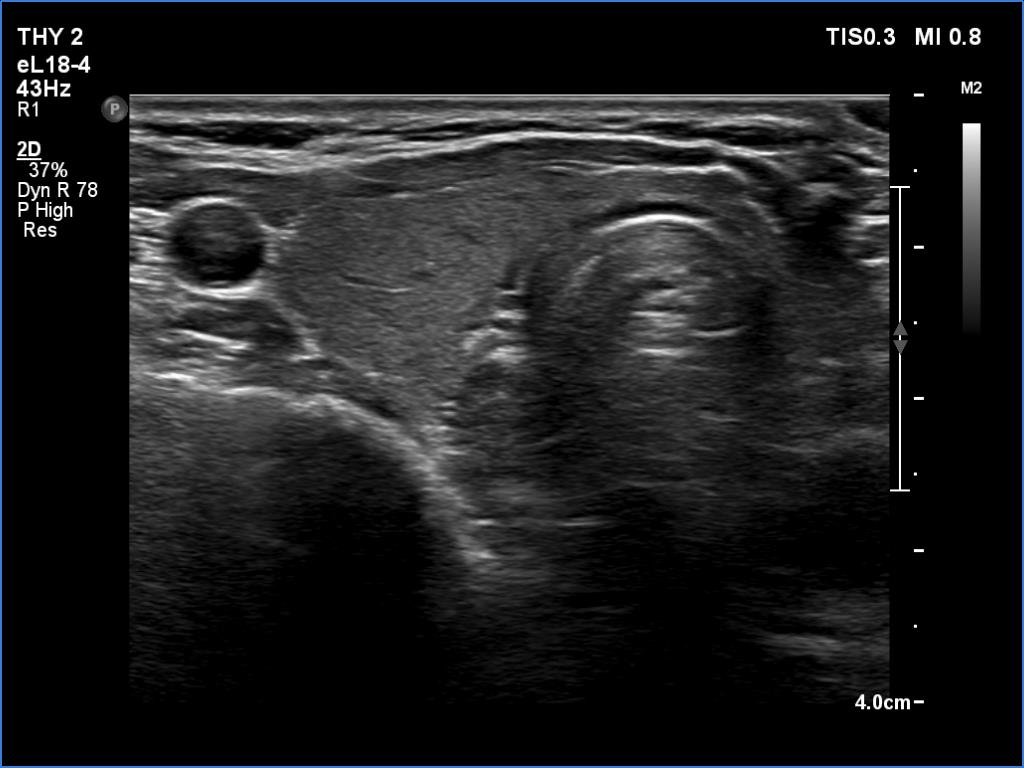

Ultrasonography. The thyroid was minimally hypoechoic and had several deeply hypoechoic discrete lesions. The latter had irregular margins and corresponded to more active foci of thyroiditis.